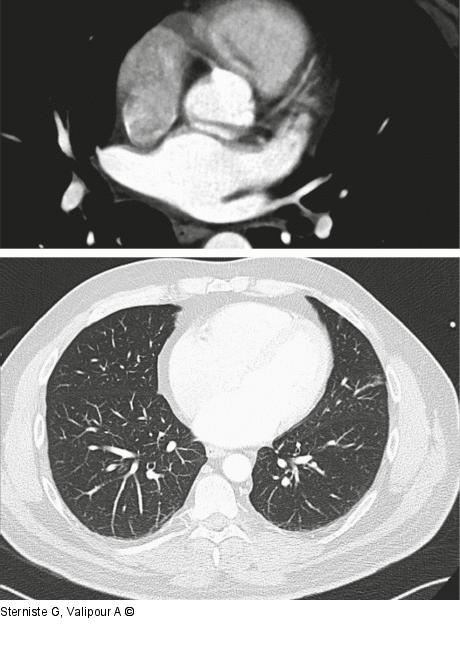

Abbildung 3: Computertomographie

Computertomographie April 2021